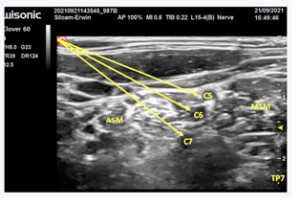

To facilitate effective medical rehabilitation, the Continuous Interscalene Block (CISB) technique with Patient Controlled Analgesia (PCA) was performed under ultrasound guidance. After the patient was positioned, anatomical landmarks, including the sternocleidomastoid, anterior scalene, and middle scalene muscles were identified. The brachial plexus roots appeared as a “cluster of grapes” on ultrasound (Figure I).

Figure I: Visualization of brachial plexus roots with "cluster of grapes" findings